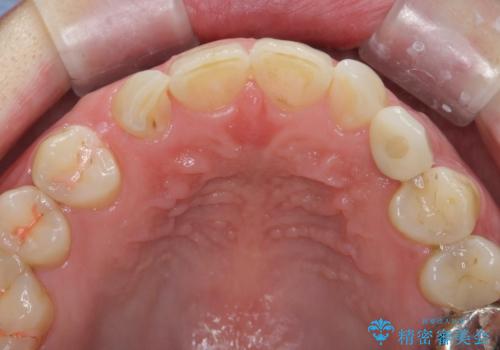

骨造成を伴う 前歯部インプラント治療

- 欠損している前歯のインプラント治療を希望され来院されました。

適切なインプラント埋入を行い、不足している骨量を補うため骨の造成を併用したインプラント治療を計画します。

前歯のインプラント治療は骨量・歯肉の厚み・インプラントの方向をしっかりと計画することで、審美的で長持ちを期待できるような仕上がりとなります。